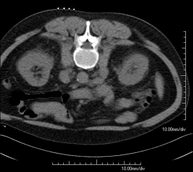

CT-guided abdominal FNA (fine needle aspiration)

It consists in obtaining a tissue sample from a specific lesion located in the abdominal cavity. This test is performed using local anaesthesia on the puncture area, which is administered with fine-gauge needles. The entire procedure is monitored using images obtained by computed tomography (CT) at various stages of the puncture, using fluoroscopy-CT equipment. After the test, the patient remains under observation in hospital for a few hours. Coagulation tests must be performed before the puncture.